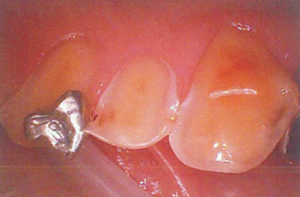

上記の成分は微アルカリ性であるために、消毒剤のpHが7.5~9になりますと歯肉の肉眼上変化はないが歯肉の細胞が溶解し細胞形態が変異します。

上記の成分は弱アルカリ性~強アルカリ性であるために、消毒剤のpHが9~14になりますと歯肉の肉眼上変化があり歯肉の細胞が溶解し細胞形態が変異します。

60分経過後

強アルカリ性のため

歯肉が溶けて骨が露出している